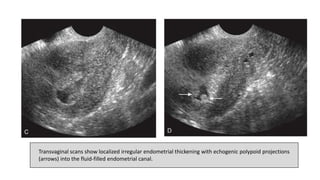

Transvaginal scans show localized irregular endometrial thickening with echogenic polypoid projections

(arrows) into the fluid-filled endometrial canal.

Transvaginal scans showlocalized irregular endometrial thickening with echogenic polypoid projections (arrows) into the fluid-filled endometrial canal.